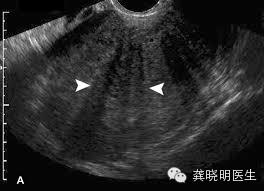

子宫肌腺症若是通过超声检查,往往可以发现子宫壁增厚,出现结构紊乱。